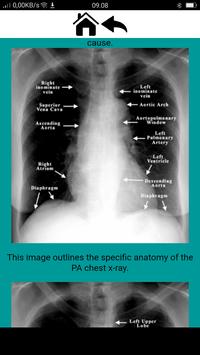

Radiographic Anatomy and Interpretation of the Chest and the Pulmonary System

The normal CXR

> Anatomy

How to read a CXR